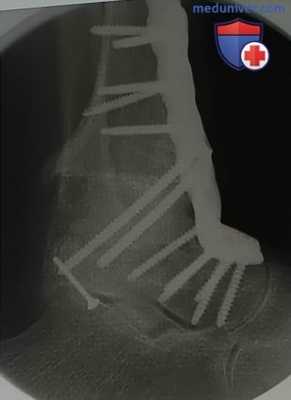

- При деформации голени или голеностопного сустава обязательна рентгенография с нагрузкой и с захватом голеностопного и коленного суставов (рис. 1)

- При наиболее сложных деформациях выполняется рентгенография в прямой проекции с захватом тазобедренного, коленного и голеностопного суставов (рис. 2)